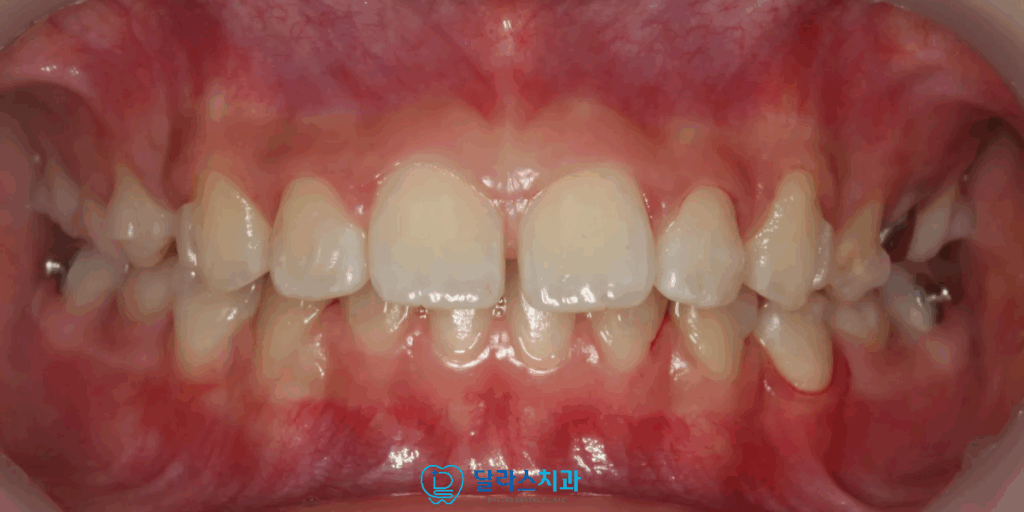

이번 노원치과 내원 환아의 경우 처음 방문 시 안모에서 돌출감이 뚜렷한 상황이었습니다,

교합 관계는 송곳니가 물리는 관계가 “full Class II”로,

즉 윗니가 아래니보다 상당히 앞으로 나온

전형적인 부정교합2급 관계를 보였습니다.

또한 위아래로 물었을 때 위쪽 앞니가 전방으로 돌출되어있는 모습을 띄어

위와 아래의 간격차이가 넓은 상태였습니다.

노원치과에서 인비절라인 퍼스트를 활용해 모든 교정이 마무리된 모습입니다.

이전에 보였던 돌출감이 모두 해소된 것을 확연하게 확인할 수 있습니다.